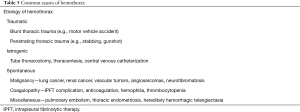

Parapneumonic effusions result from pneumonia, lung abscess, or bronchiectasis (1). While CPE is defined by the criteria as outlined in Table 1. An empyema is a severe form of CPE defined by the presence of pus in the pleural space. Some would suggest that an empyema may also be defined with a positive gram stain or culture; however, we reserve the true definition of empyema as the presence of purulent fluid (2). Empyema necessitans is a complication of poorly controlled empyema resulting in the infection eroding through the parietal pleura into the soft tissue and ultimately the skin.

The diagnosis is made by thoracentesis. Although 90% are simple and do not require drainage, early identification and treatment is vital to prevent further progression and complications (8). CPE is diagnosed by the pleural fluid analysis, while empyema occurs when the presence of purulence is noted on fluid appearance. All patients with pneumonia with an effusion should be evaluated for parapneumonic effusion. Table 1 summarizes the pleural fluid characteristics of uncomplicated parapneumonic effusion, CPE, and empyema.

The leading causes of hemothorax are blunt or penetrating thoracic trauma, and therefore the majority of cases are managed in the surgical ICU. The diagnosis of hemothorax is a surgical emergency, where there may be a need for immediate surgical exploration for the management of hemothorax (56). Rarely, a hemothorax can occur spontaneously (Table 5) (57,58).